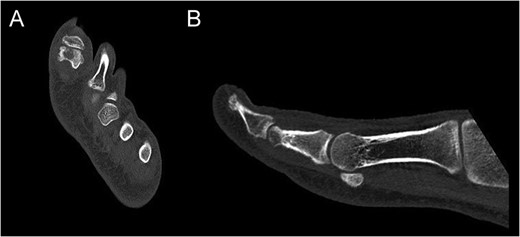

CT of the proximal phalanx of the left hallux: axial (A) and sagittal view (B), showing the recurrence of the OO and its extension to the articular surface.